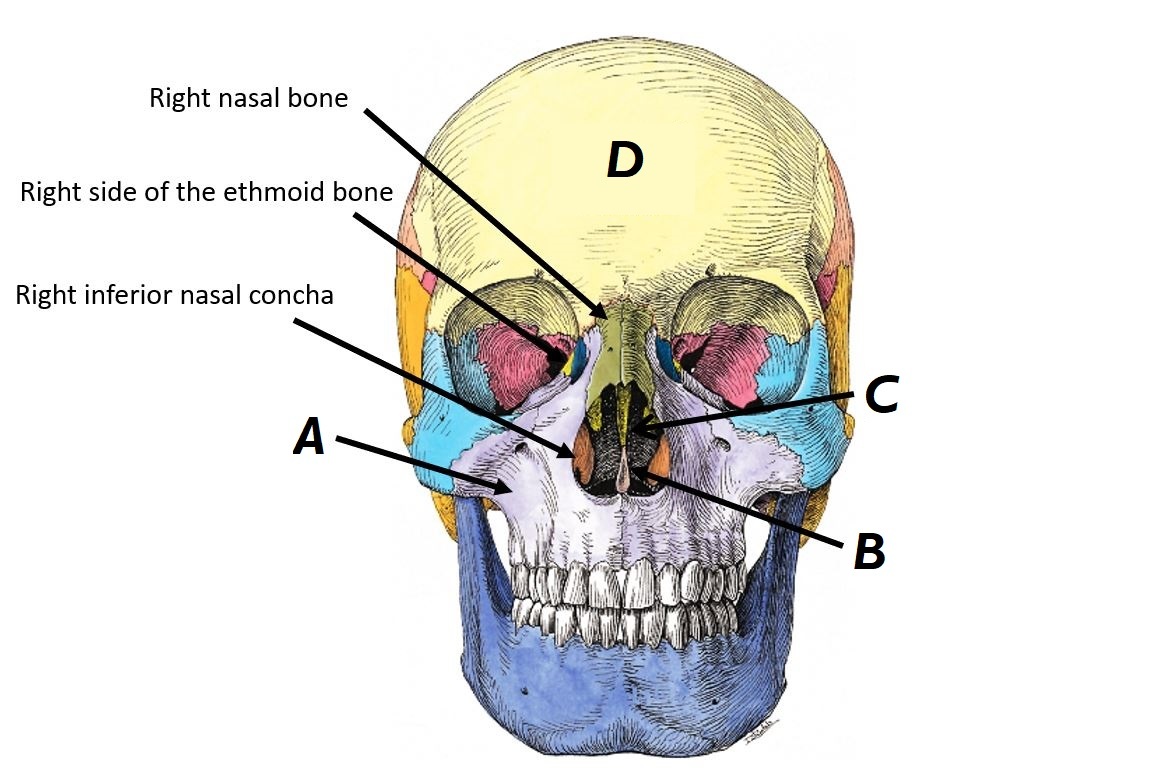

Name bones A, B and C

A - Right inferior nasal concha

B - Ethmoid bone

C - Right nasal bone

Name bones A to D

A - Right maxilla

B - Vomer

C - Ethmoid bone (perpendicular plate)

D - Frontal bone